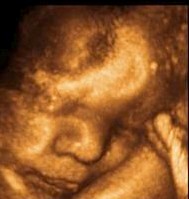

Се оформува рбетот на вашето бебе. Составен е од 33 прешлени, 150 зглобови и околу 1000 лигаменти.

Почнуваат да се формираат и најфините крвни садови и капилари, па кожата на бебето добива розов сјај. Оваа недела почнуваат да се формираат и крвните садови во белите дробови.

Просечната должина на бебето е околу 34.6 см, а просечната тежина околу 660 грама.

Бебе во 25-та седмица на бременост